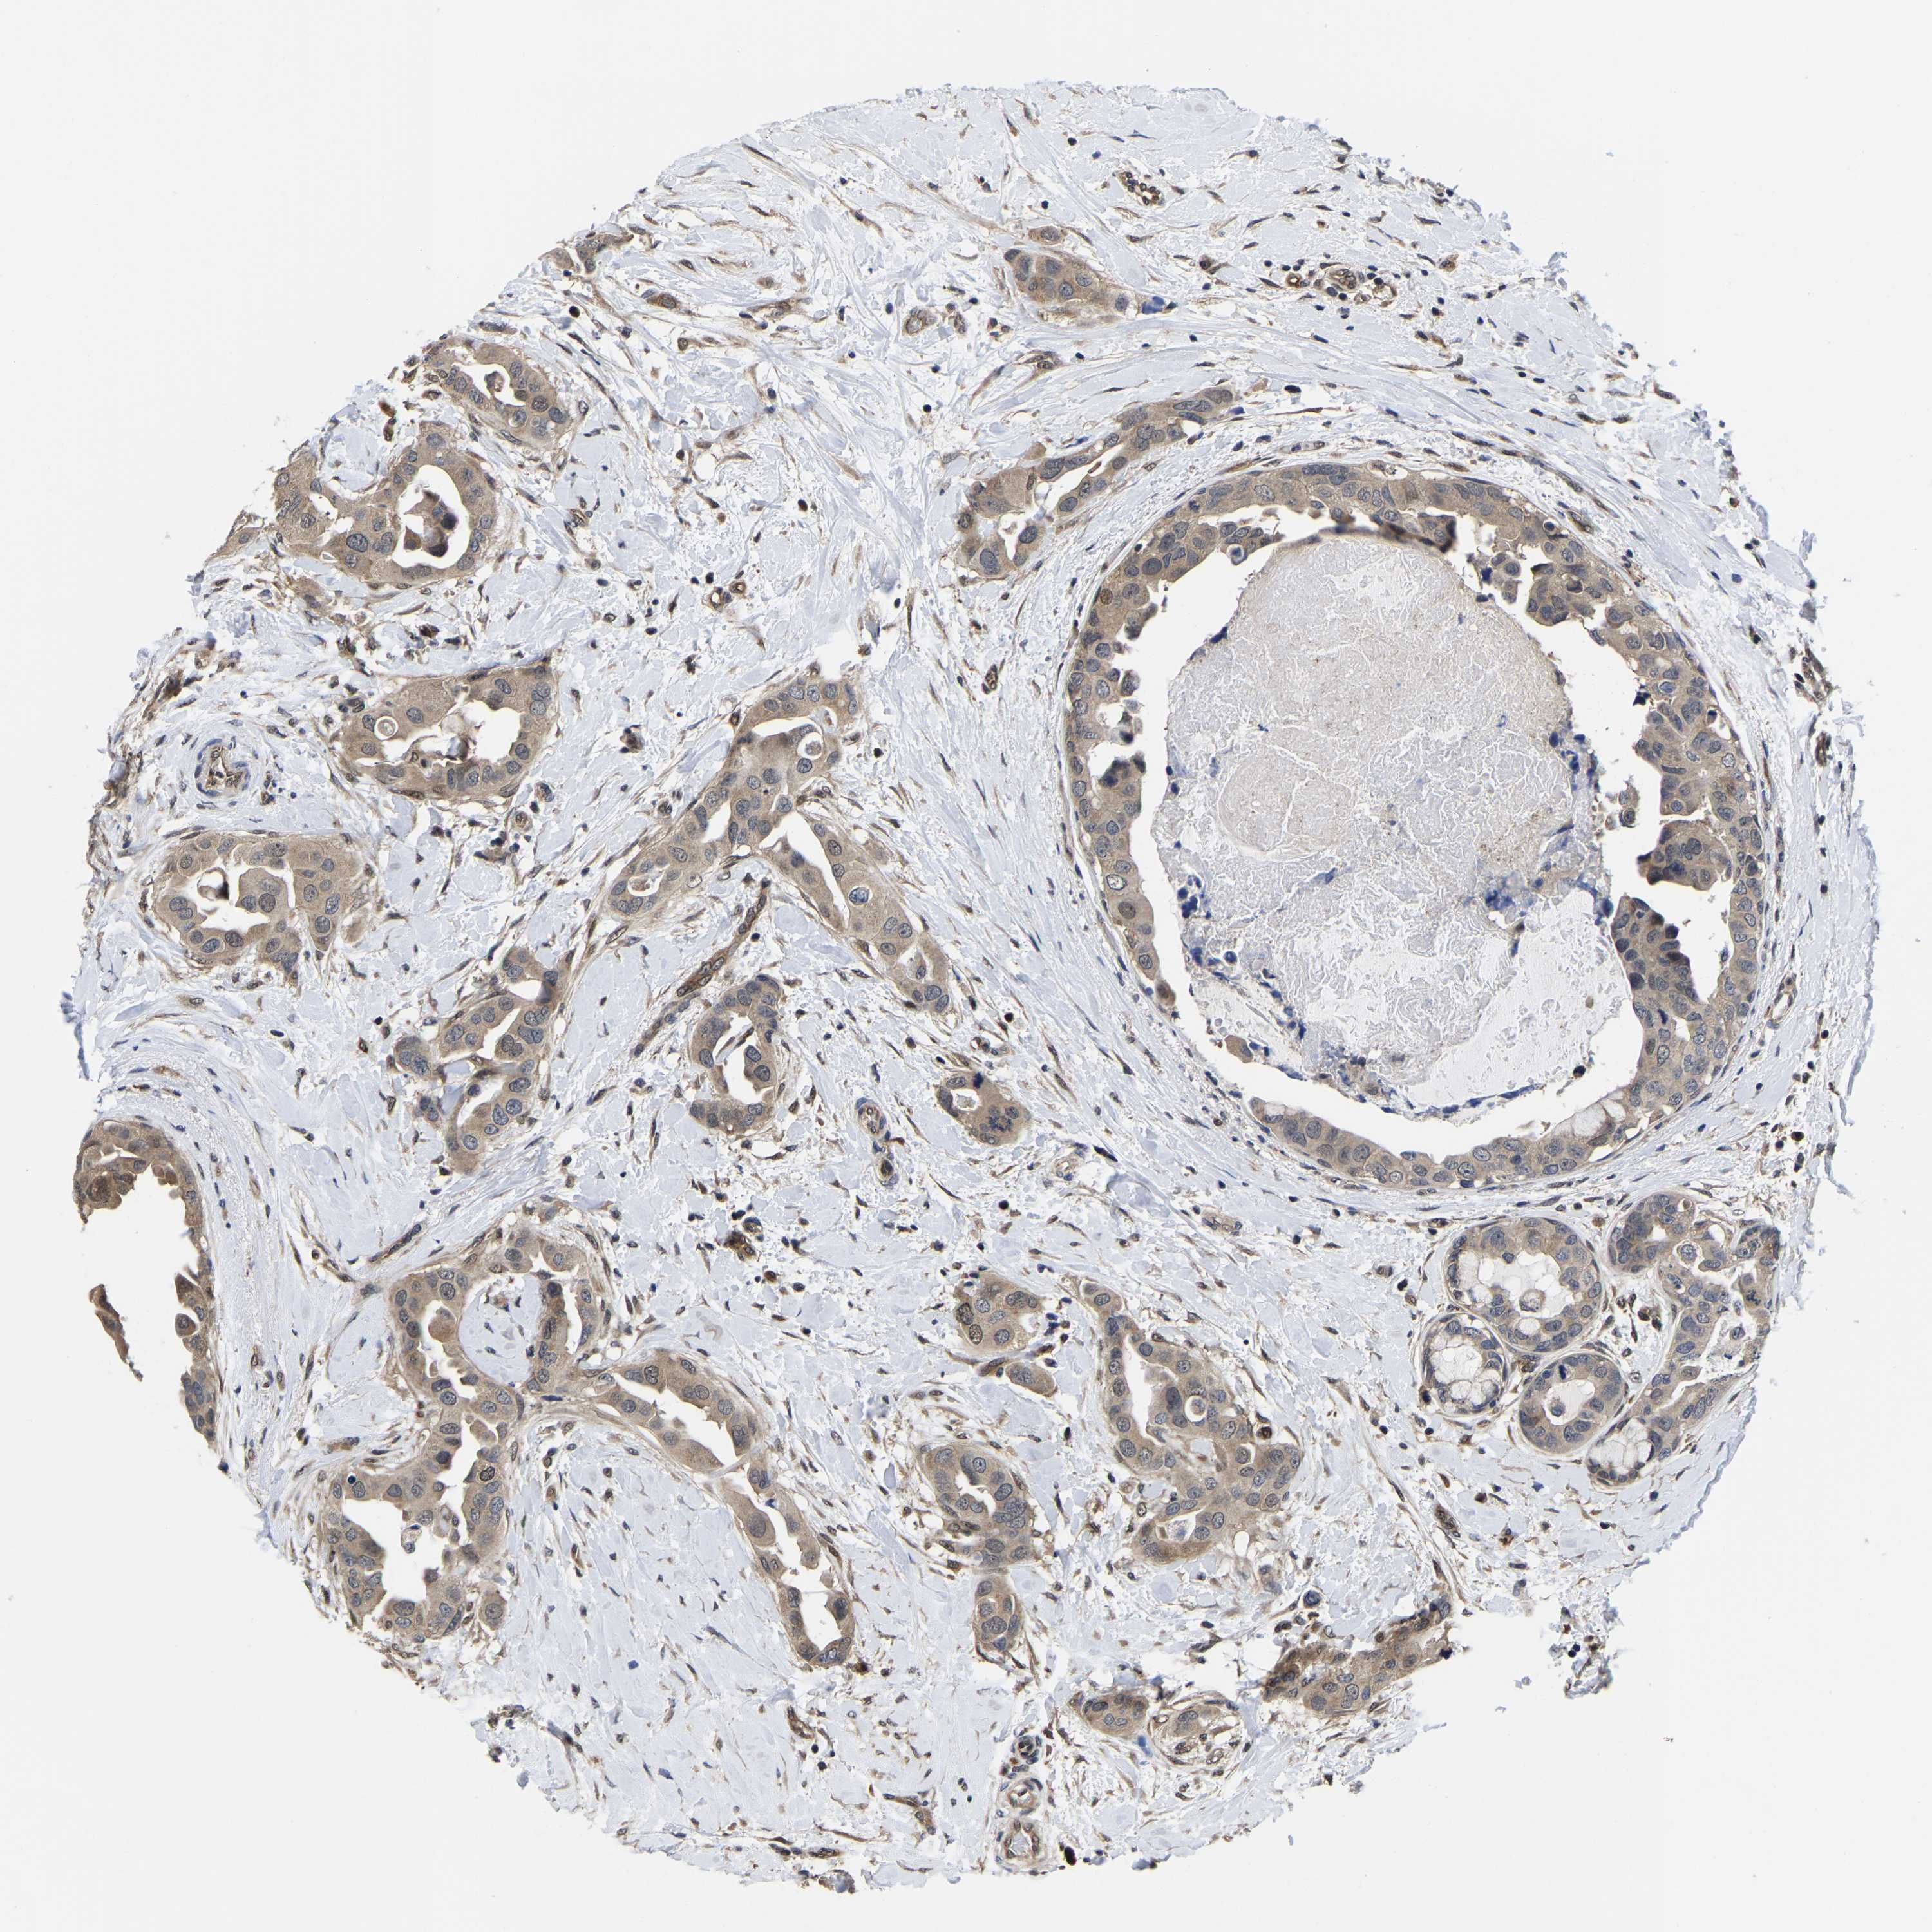

BRCA TCGA BRCA VALIDATION PROTEIN EXPRESSION

ANTIBODIES

AND

VALIDATION